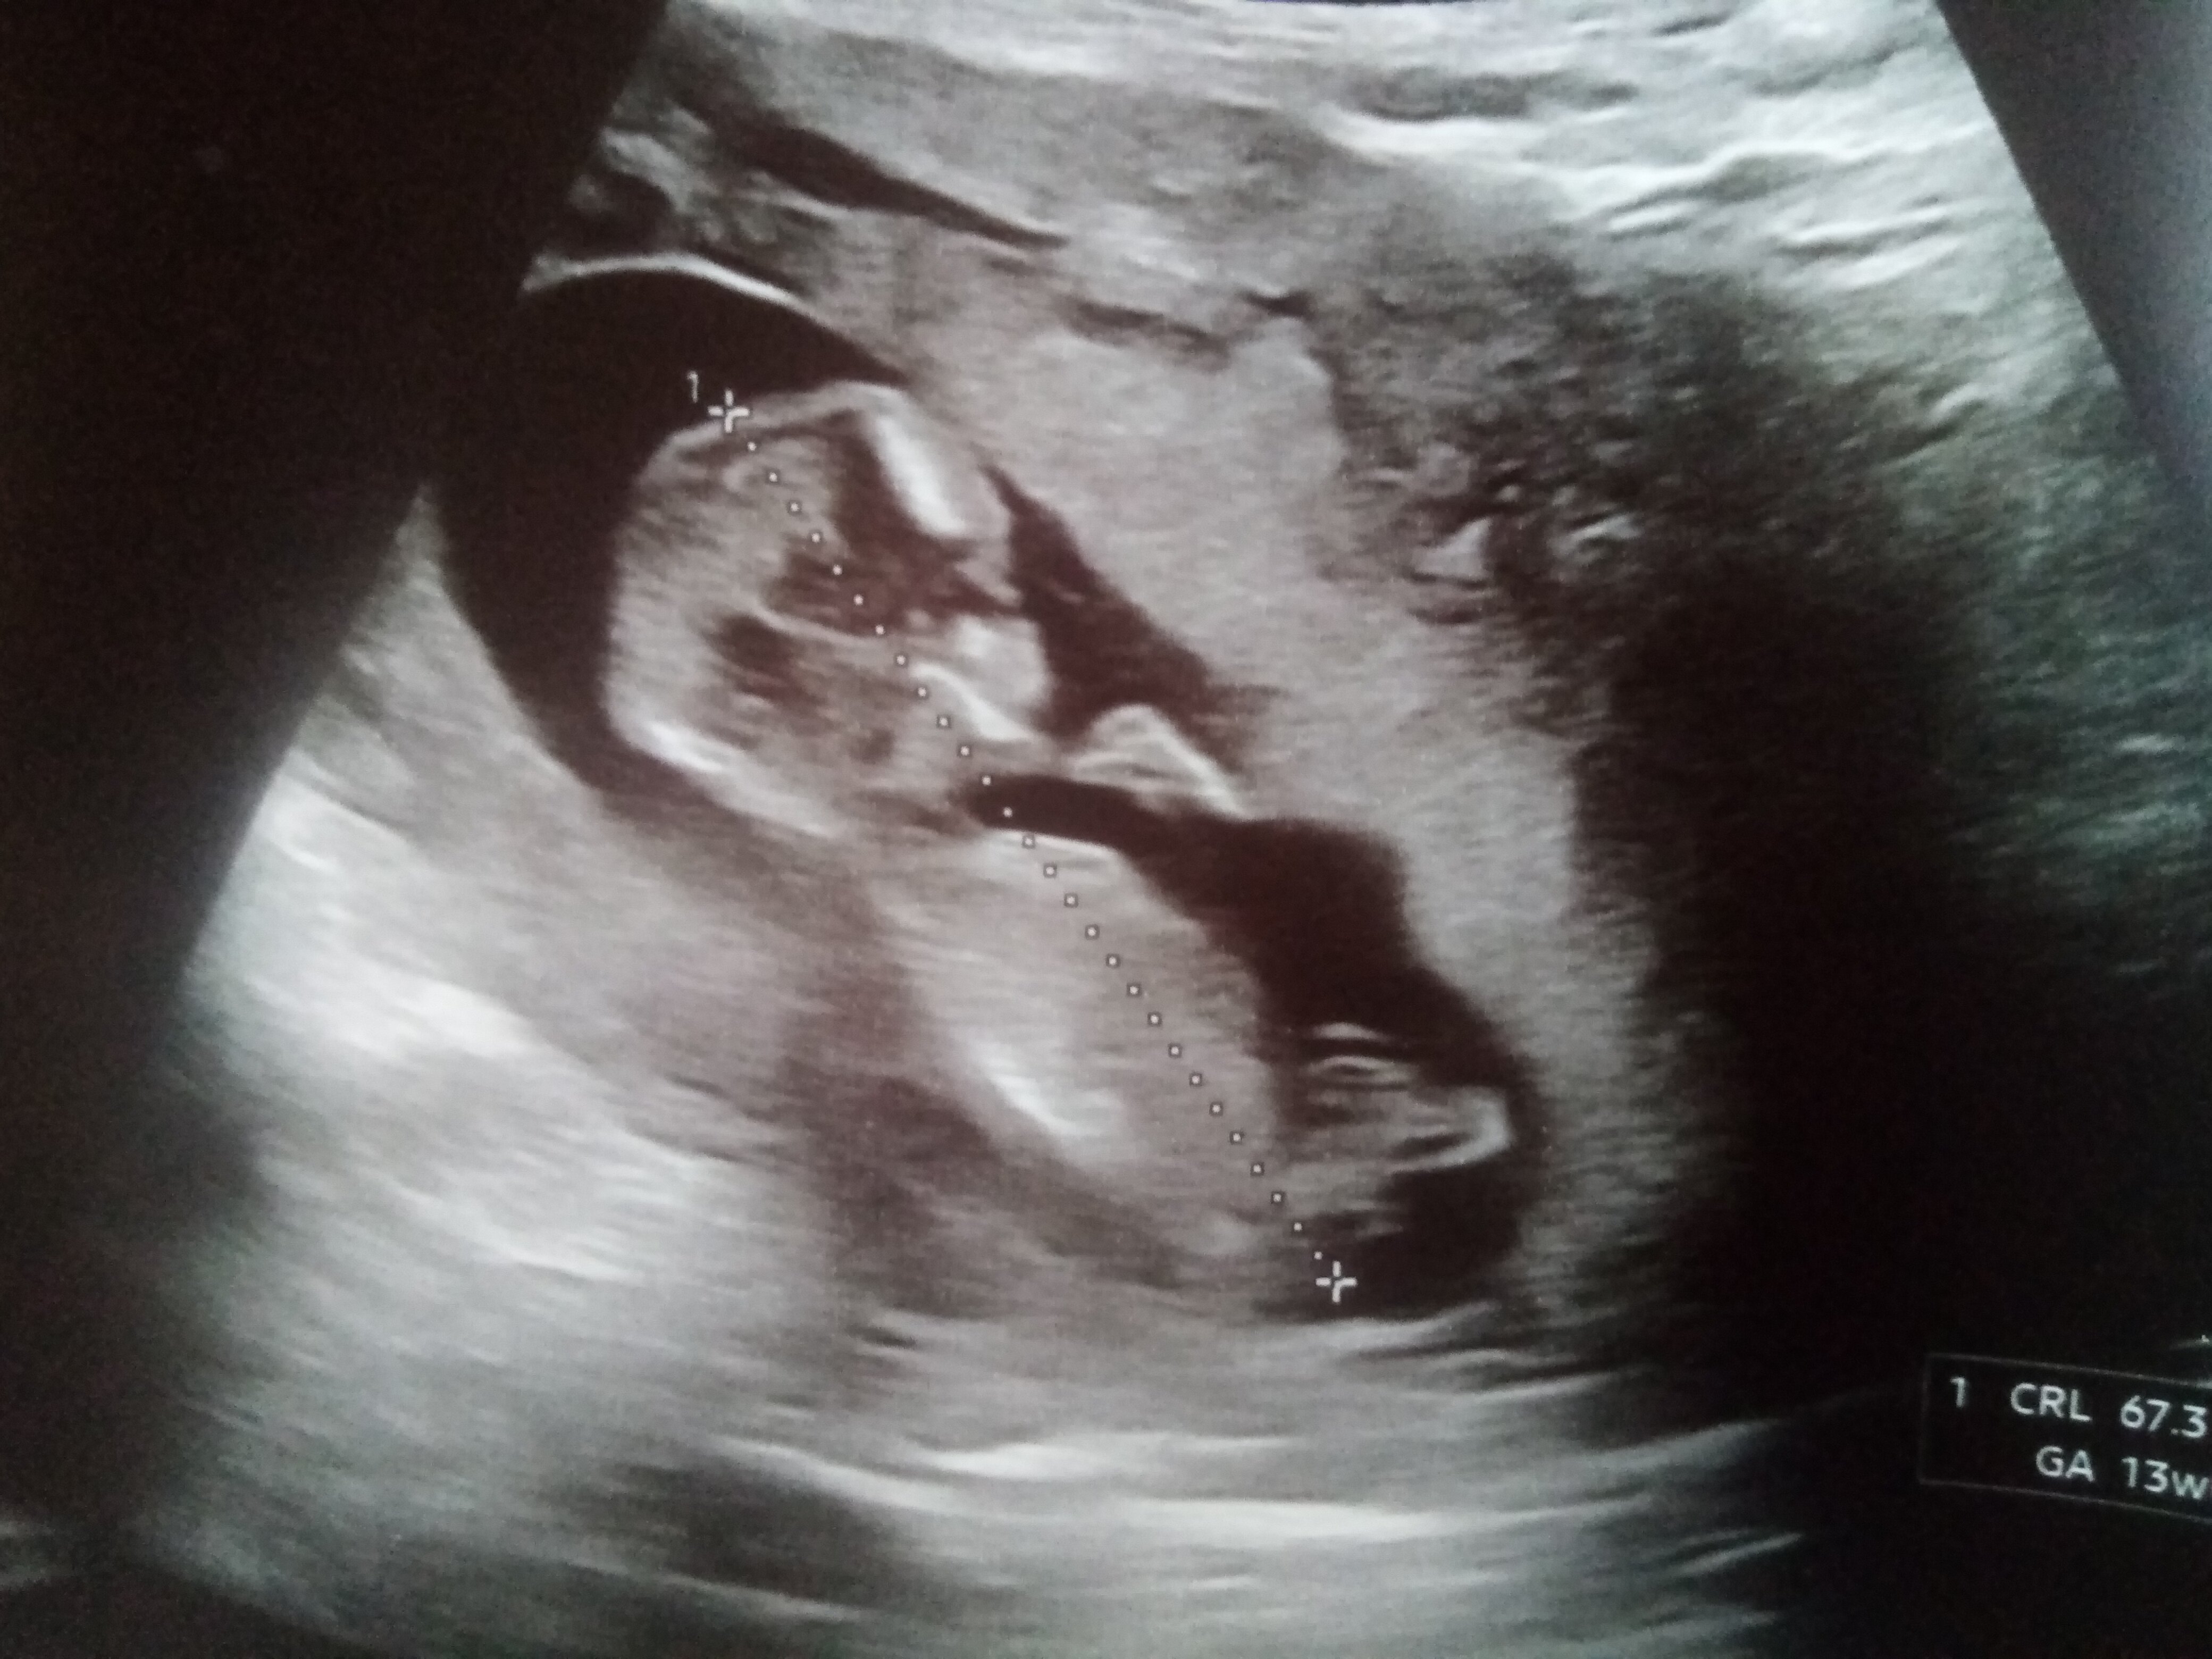

hän parkourasi pitkin kohtua, heitti voltteja ja teki 360 asteen käännöksiä ja aina niiden välissä pohdiskeli toinen käsi leualla, että mitäs sitten tekis

myooman takia on kontrolliultra joskus rakenneultran jälkeen, koska sen verran nyt kokoa ja kun kohtukin kasvaa, ettei vaan ole sit vauvalta viemässä tilaa. Mut tosi vaikea uskoa vieläkään, että tää vissiin oikeesti syntyy sit aikanaan koska ei ole vieläkään jäänyt asemalta pois

ainiin viime viikolla piti käydä pika-ajalla ultrassa toisessa kaupungissa kun torstaina tuli ihan selkeetä punertavaa vuotoa, niin on kyl aikamoista jännitysnäytelmää ollut taas! Ilmeisesti vuoto johtuu/johtui siitä, että istukka on alhaalla ja sen reuna kait vähän vuotaa. Tätäkin nyt sit seuraillaan.